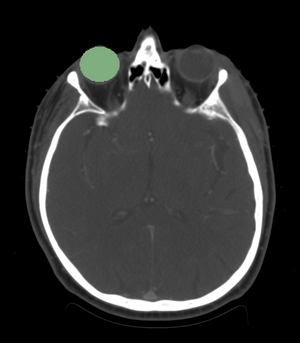

- We are interested in segmenting the eye ball, lens, optic nerve, and the optic chiasm.

- The eye ball is considered to be the pivotal organ since its segmentation will localize the region of interest when looking for other structures.

- We segmented the eye ball.